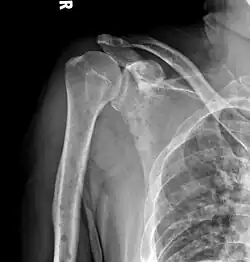

The diagnostic examination of a person with suspected multiple myeloma typically includes a skeletal survey. This is a series of X-rays of the skull, axial skeleton, and proximal long bones. Myeloma activity sometimes appears as "lytic lesions" (with local disappearance of normal bone due to resorption) or as "punched-out lesions" on the skull X-ray ("raindrop skull"). Lesions may also be sclerotic, which is seen as radiodense.[76] Overall, the radiodensity of myeloma is between −30 and 120 Hounsfield units (HU).[77] Magnetic resonance imaging is more sensitive than simple X-rays in the detection of lytic lesions. An MRI may supersede a skeletal survey, especially when vertebral disease is suspected. Occasionally, a CT scan is performed to measure the size of soft-tissue plasmacytomas. Nuclear Medicine Bone scans are typically not of any additional value in the workup of people with myeloma (no new bone formation; lytic lesions not well visualized on nuclear bone scan).

Multiple myeloma in the upper arm -